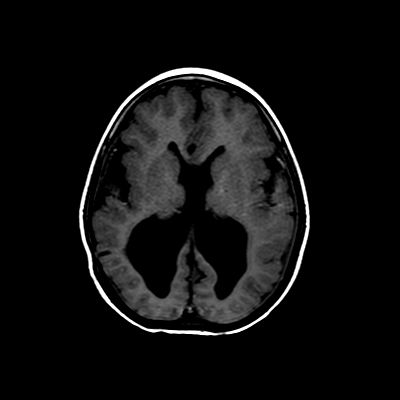

5 yaş, E

Gecikmiş motor ve mental gelişim, hipotoni, nöbet, sağ gözde glokom

Tanınız nedir?

Konjenital Kuşçular distrofi ayırıcı tanı genetik ama kas göz beyin tutulumu olması muscle eye brain düşündürüyor

Walker Warburg

Muscle eye brain disease

Konjenital muskuler distrofi( walker warburg sendromu?)

Kinkleşmiş beyin sapı. Walker warburg sendromu

Korpus kallosum disgenezisi ve kolposefali

Walker–Warburg sendromu (WWS)

Walker–Warburg sendromu (Lizensefali tip II)